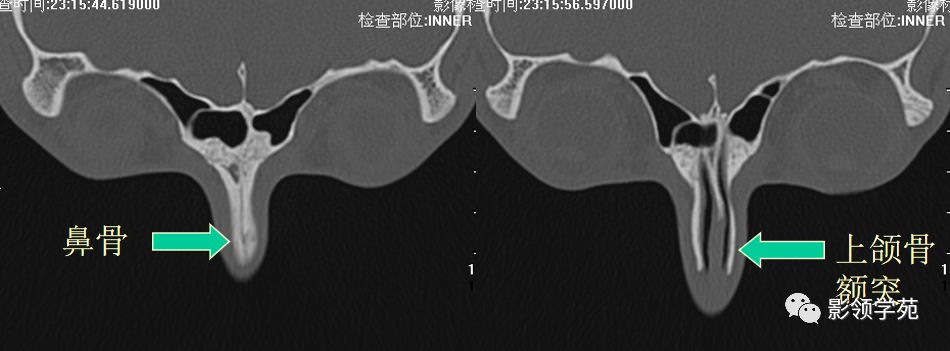

鼻骨横断面HRCT